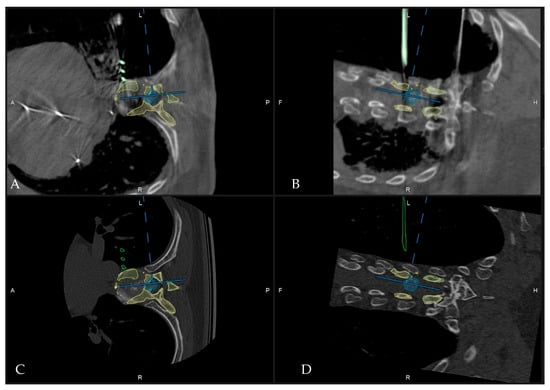

- Pojskić, M.; Bopp, M.; Saß, B.; Kirschbaum, A.; Nimsky, C.; Carl, B. Intraoperative Computed Tomography-Based Navigation with Augmented Reality for Lateral Approaches to the Spine. Brain Sci. 2021, 11, 646. [Google Scholar] [CrossRef] [PubMed]